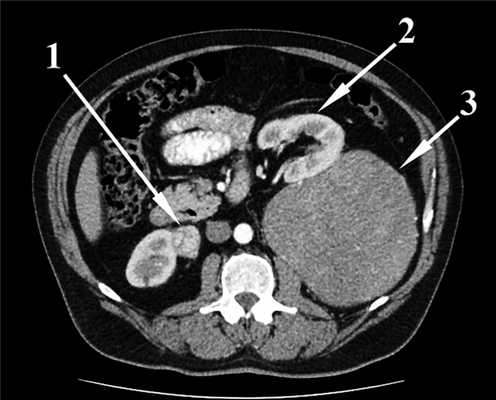

Результаты компьютерной томографии брюшной полости и забрюшинного пространства с внутривенным контрастированием подтвердили наличие неорганного объемного образования левого забрюшинного пространства, интимно прилежащего к левому надпочечнику, краниокаудальный размер которого был равен 241 мм, а максимальный поперечный размер — 143 мм. Структура образования в верхних 2/3 была относительно однородная, в нижней трети — неоднородная за счет наличия двух узлов, без контрастного усиления, что расценено как зона распада. Также визуализировано объемное образование нижнего полюса передней поверхности правой почки размером 25×27 мм с неоднородным контрастным усилением (рис. 1). Рис. 1. Компьютерная томограмма органов брюшной полости (уровень LI—II). 1 — образование нижнего полюса правой почки; 2 — левая почка; 3 — неорганная забрюшинная опухоль.